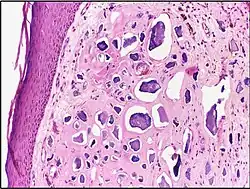

![]() |

Capillary hemangioma | Micrograph showing capillary hemangioma of skin. | Category: Histopathology of capillary hemangioma | Capillary hemangioma |